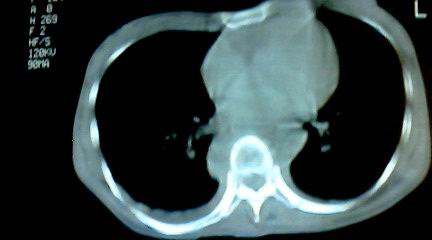

标题: CT25218:请教!胸部CT,胸8椎体骨质破坏,伴周围软组织肿。 [打印本页]

标题: CT25218:请教!胸部CT,胸8椎体骨质破坏,伴周围软组织肿。

患者,女41岁,肢体乏力。

两肺上叶继发性肺结核;胸椎结核并椎旁寒性脓肿形成。

胸椎结核并椎旁寒性脓肿形成。